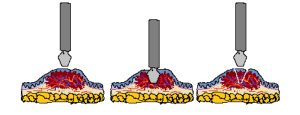

Por último se menciona la impronta y el raspaje como toma de muestra, estas últimas son

las de elección para lesiones ulcerativas y/o endofíticas; se requiere como norma para poder dar

un diagnóstico correcto descartar las primeras 2 o 3 capas cuando se realiza la toma para evitar

la contaminación y no tener un diagnóstico correcto, debido que en esas primeras hay neutrófilos,

descamación, detritus, bacterias, etc.

Biopsia incisional: puede ser realizada mediante aguja tru-cut, punch o cuña según la

neoformación y profundidad a la cual se desea llegar con la toma de muestra. Es necesario

quimioterapia neoadyuvante, cirugía reconstructiva, cirugía con electroquimioterapia

transoperatoria, etc.